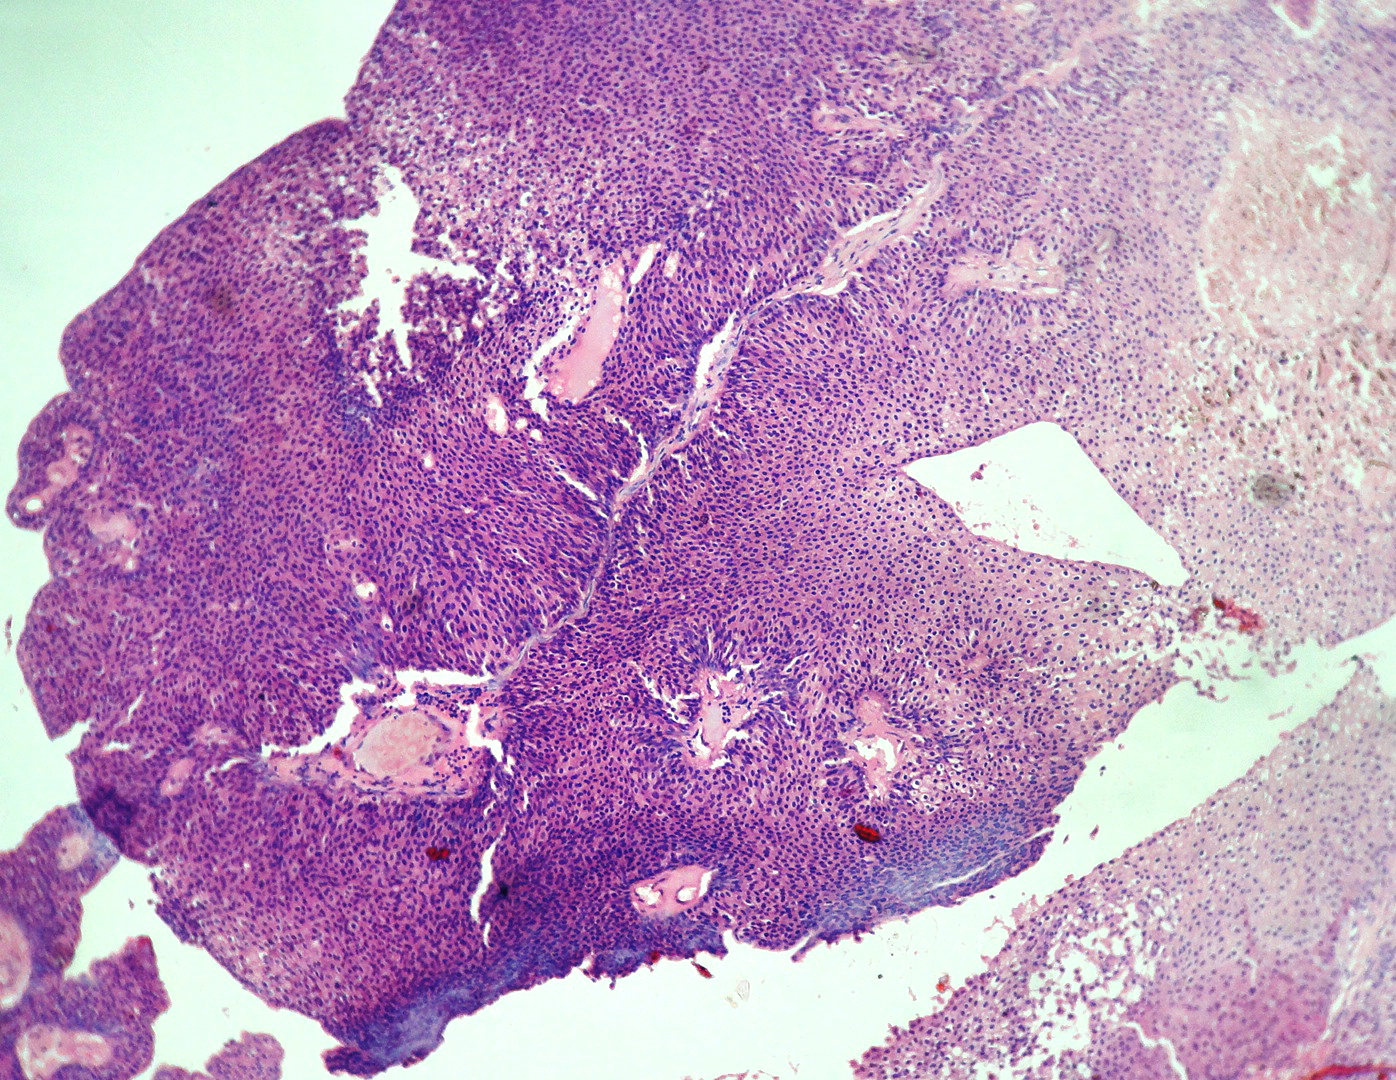

In our study, we made an attempt to evaluate the pattern of tumor growth, its degree of differentiation, progression and associated mucosal changes. In 15 cases of urothelial papilloma, it is characterized by discrete papillary growth with a central fibrovasular core lined by urothelium of normal thickness and cytology (Figure 1). In five cases of Papillary urothelial neoplasm of low grade malignant potential (PUNLMP), histopathologically the tumor is characterized by delicate, orderly, tenuous papillary structures with orderly arrangement of cells within the papillae with minimal architectural abnormalities and nuclear atypia usually limited to basal layer irrespective of cell thickness (Figure 2). The major distinction from papilloma is that in PUNLMP the urothelium is much thicker and nuclei are significantly enlarged. In 21 cases of low grade urothelial carcinoma, histologically it is characterized with papillary axes which are more compact, crowded, fused at the base and lined by unordered cells showing both architectural and cytological abnormalities with frequent mitosis (Figure 3). In 51 cases of high grade urothelial carcinoma showed fused papillary axes over the large areas resulting in sheets and solid areas. The cells have enlarged, hyperchromatic, pleomorphic nucleus in full thickness of the epithelium with increased atypical mitosis (Figure 4). As per TNM staging used in our study we observed majority of the bladder tumours were invasive accounting for 78.25% (Figure 5 & 6) as compared to non-invasive bladder tumours constituting 21.73% of the cases as shown in table 3.

Figure 2 Papillary urothelial neoplasm of low malignant potential shows delicate papillae lined by hyperplastic urothelium with minimal nuclear atypia (H and E stain, 100X).

Figure 3 Low grade papillary urothelial carcinoma shows compact, crowded papillae lined by hyperplastic urothelium with moderate nuclear atypia (H and E stain, 100X).